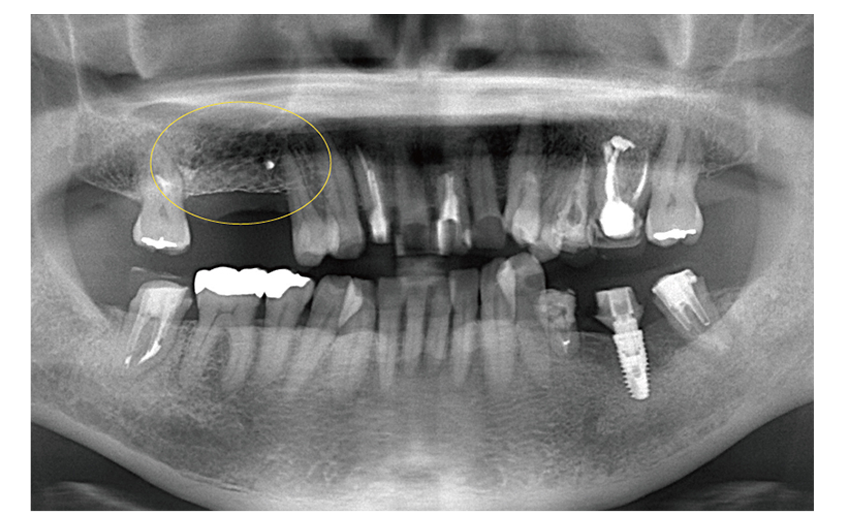

第二大臼歯のな根が折れており抜歯と診断

第一大臼歯がすでに欠損しているのでこのままだと奥歯が2本失ってしまう為、第二大臼歯に親知らずを移植し、第一大臼歯部はインプラント治療を計画した。

治療期間 1年

費用 60万円(インプラント45万 / 歯の移植15万)

| メリット | 親知らずを移植することでインプラントの本数を減らして費用を抑えることができる |

|---|---|

| デメリット | 歯の移植はインプラントに比べて成功率が低い |